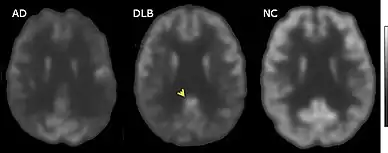

MRI of brain showing hippocampus atrophy (red rectangles), more prominent in AD than DLB, compared to normal control (NC)

FDG-PET horizontal cross section of brain, with brighter areas indicating higher metabolism. The cingulate island sign is indicated by the arrowhead.

FDG-PET of brain surface, with the color red indicating areas of high metabolism. The occipital lobe in DLB (arrows) shows less activity than in AD.

PET or SPECT imaging can be used to detect reduced dopamine transporter uptake and distinguish AD from DLB.[57][149] Severe atrophy of the hippocampus is more typical of AD than DLB.[150] Before dementia develops (during the mild cognitive impairment phase), MRI scans show normal hippocampal volume. After dementia develops, MRI shows more atrophy among individuals with AD, and a slower reduction in volume over time among people with DLB than those with AD.[33] Compared to people with AD, FDG-PET brain scans in people with DLB often show a cingulate island sign.[33]